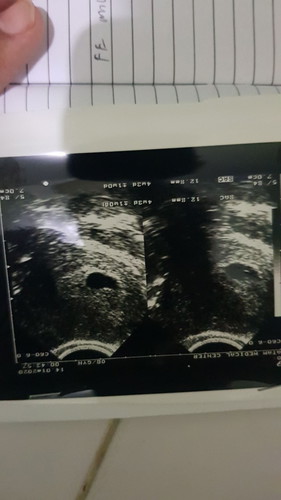

USG Kantung Kehamilan

Halo, Alhamdulillah saya dan istri diberi rejeki tahun ini. Istri dinyatakan hamil, tp setelah USG Kantung kehamilan gak bulat sempurna. Apakah ini normal?

Halo Bu, Sudah kontrol, Ini kehamilan kedua. Sebelum nya juga seperti ini kantung nya. Tapi qadarullah, istri keguguran. Jadi makin parnoan. Kata dokter In Syaa Allah gamasalah disuruh bed rest total.